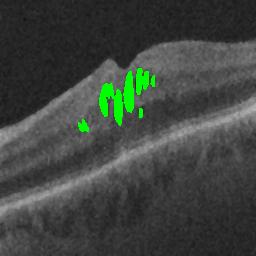

The qualitative results of the proposed system is shown in the Fig. 3. The detection task is evaluated using Area Under the Curve(AUC) metric and the segmentation task is evaluated using Dice Coefficient(DC) metric and the results are presented in Table1

| (a) De-noised OCT slice | (b)Predicted fluid region | (c)Manual fluid segmentation |

|

|

|

| (d) De-noised OCT slice | (e)Predicted fluid region | (f)Manual fluid segmentation |